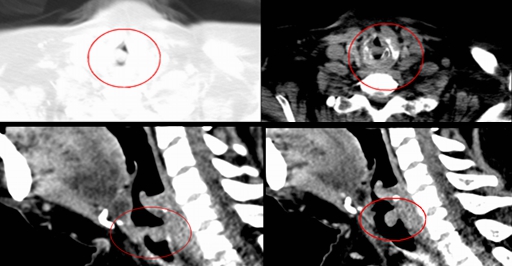

患者为48岁中年女性,因颅内出血在行“气管插管全麻下颅内多发血肿清除+去骨瓣减压术+颞肌颞浅动脉贴敷+侧脑室穿刺外引流术”,术后康复治疗期间因出现呼吸困难,夜间为甚,伴有明显喘鸣音,完善CT检查提示:声门下气管内新生物,占据气管内径80%以上,仅靠两侧缝隙通气。

经过多科室会诊,呼吸与危重症医学二科主任王先勇在了解患者病史及喉部增强CT后,认为其声门下肿物随时可能因患者少量的痰液引起气道堵塞,从而导致窒息的发生,需尽快切除患者的气管肿物。

患者CT资料